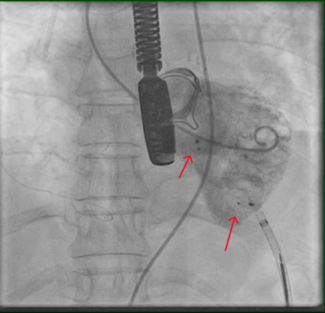

Bilateral femoral arterial access was obtained using 8 Fr 45 cm long sheaths. The RCA was initially engaged with an 8 Fr JR4 guide that provided poor to moderate support. The left main was engaged with a XB 3.5 guide. Coronary angiography using dual injection demonstrated marked calcification in the RCA with a 30 mm mid level occlusion (Figure 1A). The mid RCA filled via collaterals from the LAD and the circumflex and reconstitution of the mid RCA occurred at the site of origin of a large acute marginal branch.

We attempted to wire retrogradely, but were unable to cross through septal collaterals in part due to a previously placed LAD stent. We engaged the RCA with a 7 Fr Champ 2 guide and wired into the acute marginal distal to the CTO using a Pilot 150 wire (Abbott Vascular) through a Finecross microcatheter (Terumo) (Figure 1B). We encountered severe difficulty crossing the CTO with a balloon. We inflated several 1.5 mm balloons into the lesion but were unsuccessful in crossing. We used a 7 Fr Guideliner catheter (Vascular Solutions) to deeply engage the RCA and were then able to cross with a 1.5 mm balloon. We predilated several times with 1.5 mm and 2.0 mm balloons, restoring antegrade flow through the RCA CTO (Figure 1C).

We could not wire antegradely into the mid RCA in spite of using multiple wires, as there was an acute bend at the origin of the acute marginal branch. We eventually used a "hairpin wire" technique, in which a Whisper wire (Abbott Vascular) was bent approximately 3 cm from its tip, advanced into the acute marginal branch, and pulled back (Figures 1D and 1E). We then attempted to advance a balloon into the distal RCA, but were not successful and in the process, the guidewire and guide catheter position were lost.